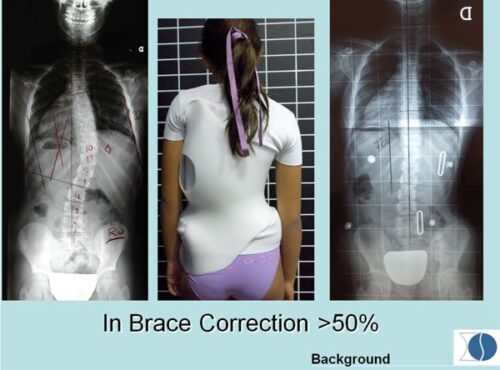

1. الأشعة داخل الحزام (IB-XR)

هي الأشعة التي تُؤخذ أثناء ارتداء الحزام، وتهدف إلى قياس مدى “تصحيح العمود الفقري” بشكل فوري.

كان يُعتقد سابقًا أن هذه الأشعة هي المعيار الأساسي لتقييم نجاح الحزام، حيث اعتبر بعض الأطباء أن نسبة تصحيح تتراوح بين 25% إلى 50% داخل الحزام تشير إلى نتائج جيدة.

لكن المشكلة هنا أن هذه الأشعة لا تعكس الواقع الكامل، لأنها تقيس التأثير الميكانيكي للحزام فقط.

2. الأشعة بعد الخروج من الحزام (FOB-XR)

هي الأشعة التي تُؤخذ بعد فترة قصيرة من خلع الحزام خلال اليوم، وتُعتبر أكثر واقعية لأنها تُظهر:

- قدرة العمود الفقري على الحفاظ على التصحيح

- قوة العضلات

- التوازن العصبي العضلي

وهنا تظهر أهمية كبيرة، لأن الهدف الحقيقي من العلاج ليس فقط “تصحيح مؤقت”، بل الحفاظ على التحسن بدون دعم خارجي.

الدراسات الحديثة أظهرت نتيجة مهمة جدًا:

الأشعة بعد الخروج من الحزام (FOB-XR) تتنبأ بنتائج العلاج النهائي بشكل أفضل من الأشعة داخل الحزام (IB-XR).